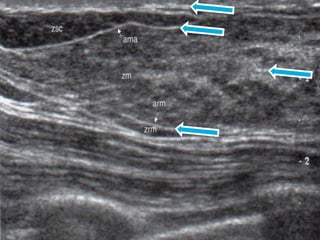

Anatomía Mamaria por USG

 ESTRUCTURAS ANATOMICAS

PRESENTAN ECOGENICIDAD VARIABLE

 GRIS MEDIO – HIPERECOICAS

 HIPERECOICAS: TFE INTERLOBULAR

COMPACTO, APONEUROSIS MAMARIA

ANT Y POST, LIG. DE COOPER,

PAREDES DE LOS CONDUCTOS Y PIEL

 ECOGENICIDAD MEDIA (ISOECOICAS):

GRASA, TEJIDOS EPITELIALES DE

CONDUCTOS, Y LOBULOS, TFE

INTRALOBULAR Y PEREIDUCTAL LAXO.

 TEJIDO MAMOGRAFICAMENTE DENSO:

EN USG CORRESPONDE A TEJIDOS

ISOECOICOS O HIPERECOICOS-

ISOECOICOS MIXTOS